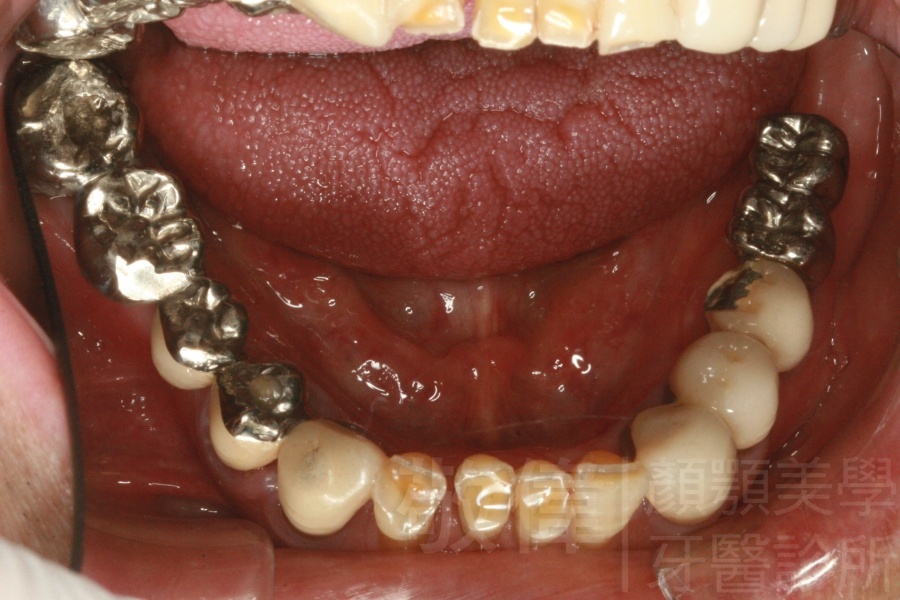

治療前上顎   治療前正面   治療前下顎

治療後上顎   治療後正面   治療後下顎